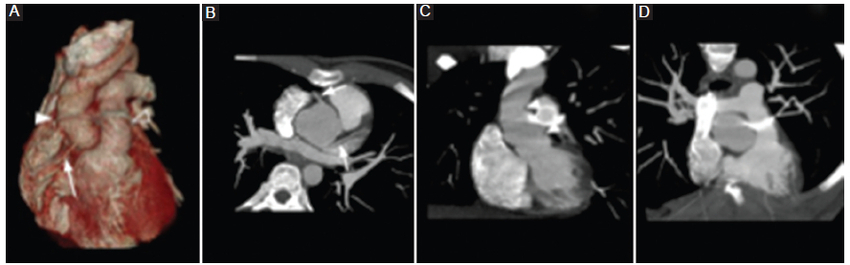

Cambios posoperatorios agudos

La visualización de colecciones líquidas homogéneas de baja densidad o áreas de aumento de la densidad de partes blandas periinjerto son hallazgos esperables en los procedimientos de la aorta torácica ascendente. Estas se han asociado con una reacción inflamatoria al material sintético del injerto o un tejido fibroso organizado posterior a un hematoma posoperatorio. Estas colecciones no realzan tras la administración de contraste intravenoso y se pueden resolver espontáneamente. La presencia de burbujas de aire en el mediastino (neumomediastino) es esperable durante el posoperatorio temprano. Sin embargo, estas cualidades deberían ser merecedoras de mención cuando son nuevas, incrementan de tamaño o persisten por más de 6 semanas (Fig. 7) (1,2,3.

Cambios posoperatorios crónicos

La fase sin contraste es de vital importancia para diferenciar las estructuras posquirúrgicas hiperdensas normales de las posibles complicaciones, como son la extravasación del material de contraste y los pseudoaneurismas. El dacrón es el material empleado en las prótesis y se observa de bordes redondeados, paredes lisas y ligeramente hiperdenso en las fases sin contraste intravenoso, lo cual puede simular un pseudoaneurisma. Este último se diferencia por su presentación típica en forma de lesiones hipodensas o isodensas en las imágenes sin contraste (Fig. 8) (3,4,5,6,7,8.

Otro dato a tener en cuenta son las tiras de fieltro que pueden verse alrededor del injerto, como en los sitios de colocación de la cánula arterial, al igual que el lugar de la anastomosis de la arteria coronaria (técnica del botón) (Fig. 9). Estas tiras también se observan espontáneamente densas en las fases sin contraste, pudiendo asemejar extravasación del contraste o un pseudoaneurisma (Fig. 10) (8. Otra manera de diferenciar un pseudoaneurisma es la ubicación, debido a que las tiras de fieltro y de dacrón suelen encontrarse a lo largo de toda la circunferencia de la anastomosis, mientras que un pseudoaneurisma estaría ubicado excéntrico a lo largo de una sola pared. En las fases poscontraste, el injerto suele ser indistinguible de la pared nativa8.

Los pseudocolgajos son visualizados como una banda lineal hipodensa generada por una leve angulación del injerto, en ocasiones confundido con una disección aórtica real, al no ser examinado en múltiples planos (Fig. 11) (8.

Por último, las áreas de realce u ocupación en el espacio generado entre la raíz del injerto y la envoltura aórtica nativa circundante, así como en la anastomosis del botón de la arteria coronaria, pueden hacer sospechar una dehiscencia o una rotura. Sin embargo, en las técnicas de inclusión, como la de Cabrol, pueden visualizarse con relativa frecuencia y se consideran como hallazgos esperables en el contexto clínico de un paciente asintomático. Pueden persistir sin modificaciones imagenológicas por un largo periodo de tiempo (Fig. 12) (9.